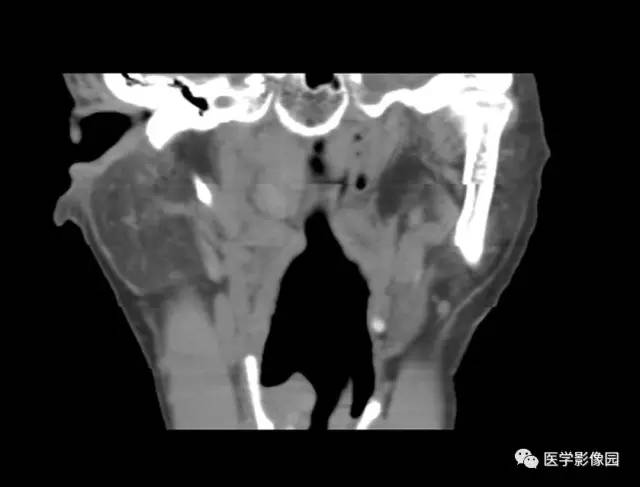

图3-5-16全喉型癌

B.肿瘤向上生长,占据整个喉前庭部,

左颈部见增大淋巴肿融合成团块(↑)